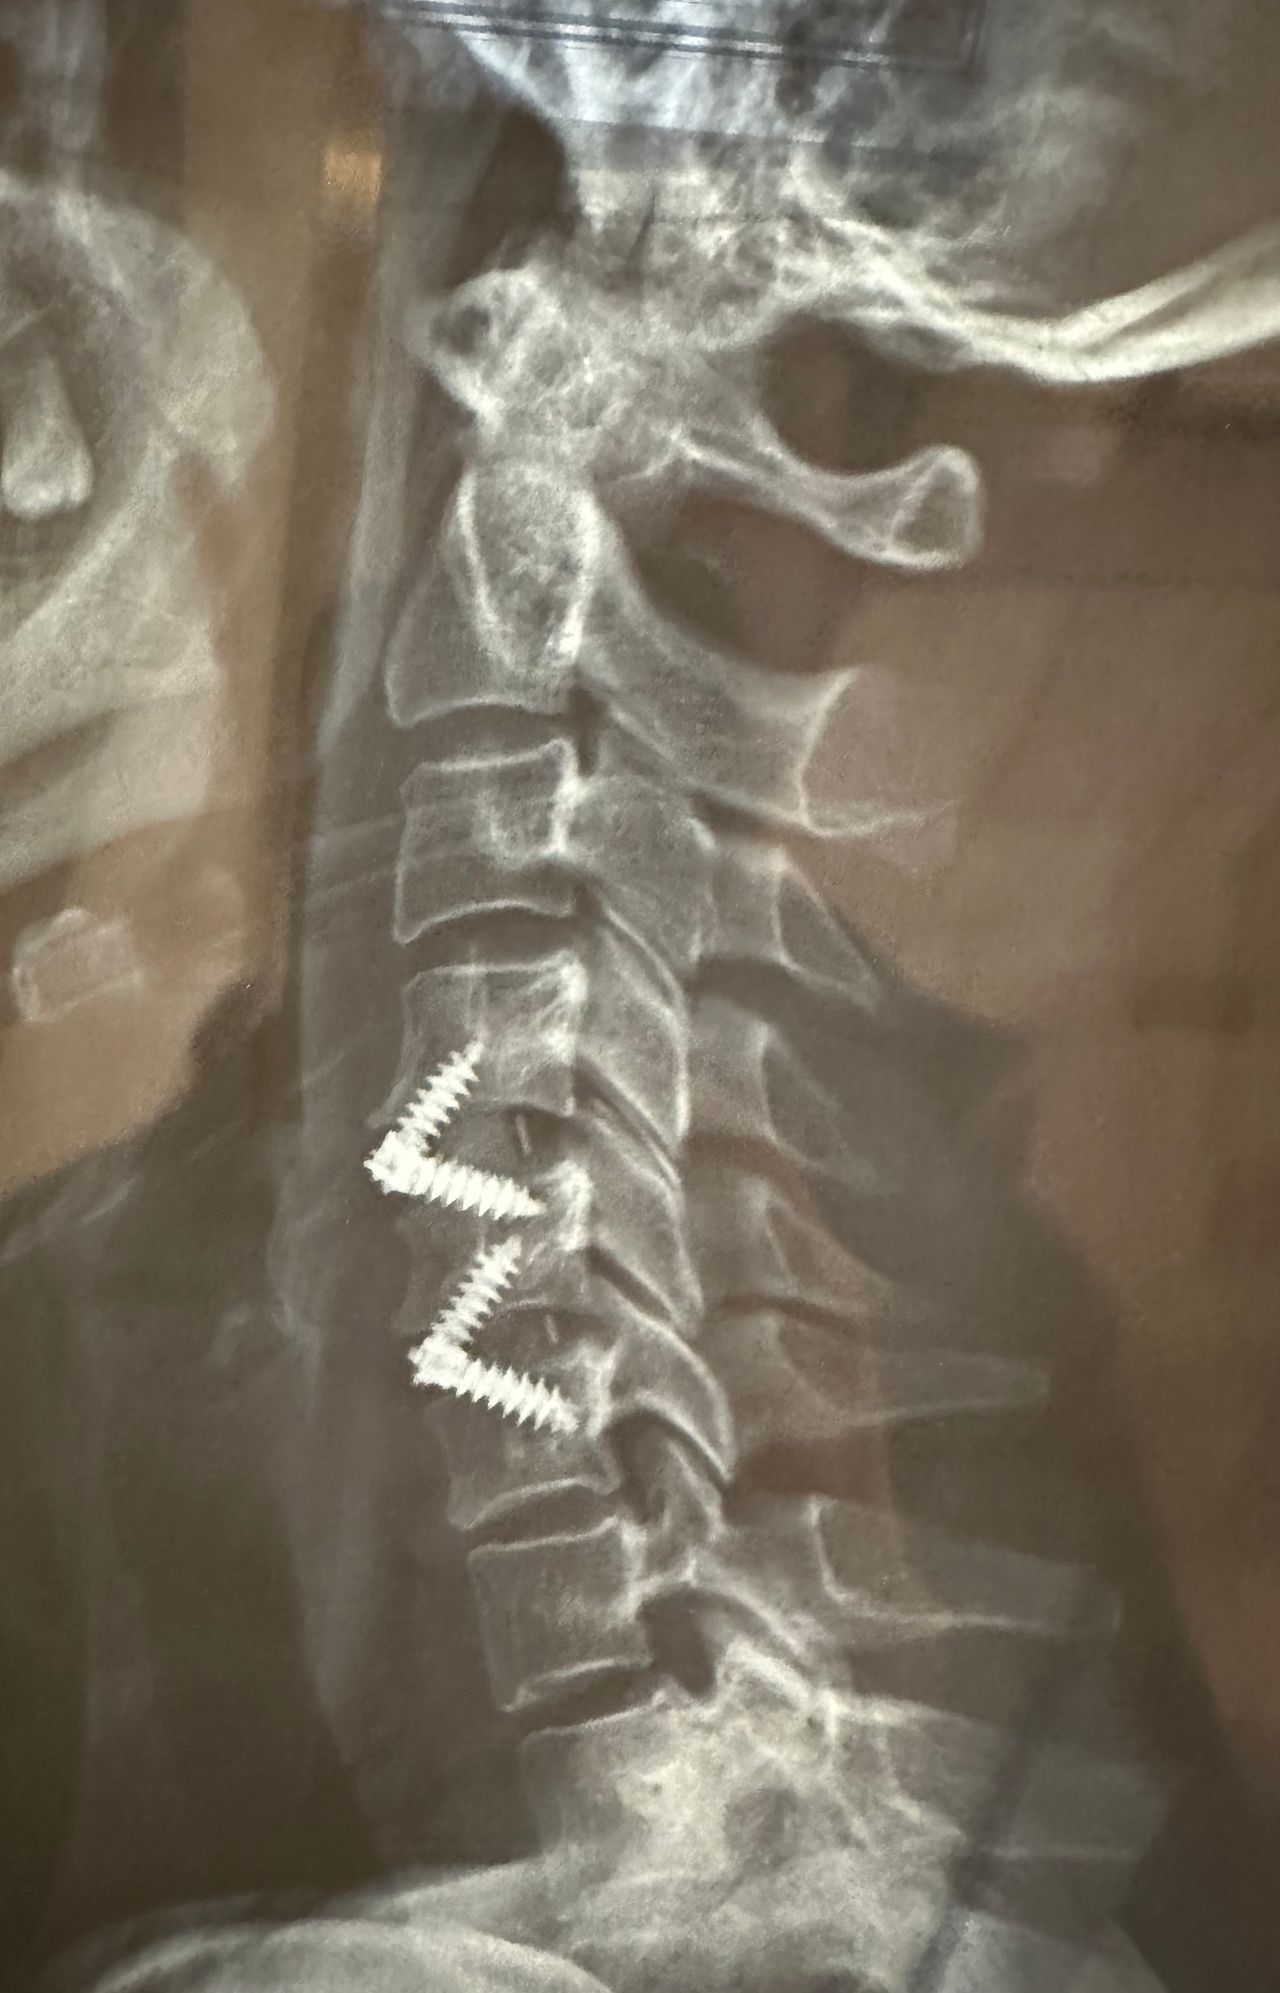

- Chirurgia Mininvasiva percutanea vertebrale - stabilizzazioni e artrodesi intersomatiche (per fratture vertebrali, spondilolistesi, instabilità vertebrali, discopatie)

- Impianti protesici di ultima generazione, massima integrazione con l’osso e maggiore durata negli anni

- RX scopia intraoperatoria